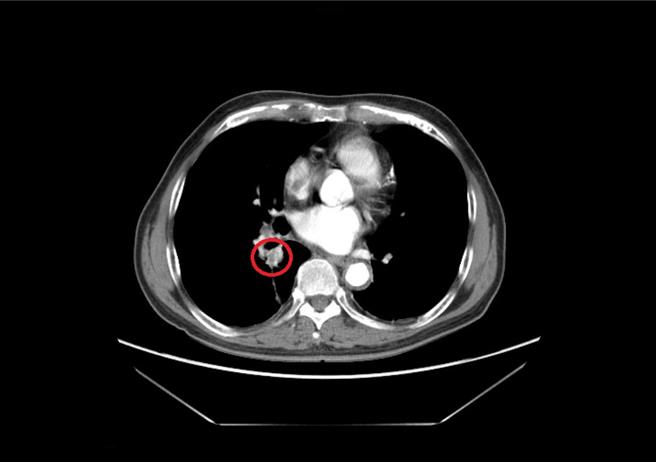

近年于大千接受肺癌治疗的病人中,谢为忠分享两个案例,第一位是80岁的男性,于2020年因胸闷、喘,从他院转至大千就医,经检查后为第四期肺腺癌。因肿瘤有EGFR的基因突变,因此申请使用泰格莎,治疗至今将近四年,其右下肺叶肿瘤从一开始的2.5公分,到现在缩小为1.3公分。另一位57岁的男性,于2022年因为慢性咳嗽2、3个月未痊癒,而到门诊就医,检查发现左上肺叶有一将近3公分的肿瘤,同样为肺腺癌第四期,且癌细胞侵犯到骨头、大血管及脑部,同时有EGFR的基因突变,在使用泰格莎治疗2年后,目前肿瘤已缩小至不到1公分。两位个案在治疗期间,每三个月需评估疗效是否稳定或进步,才能给付下一次的疗程,由于药物副作用较轻,日常作息仍可活动自如,甚至继续工作至退休,生活皆不受影响。